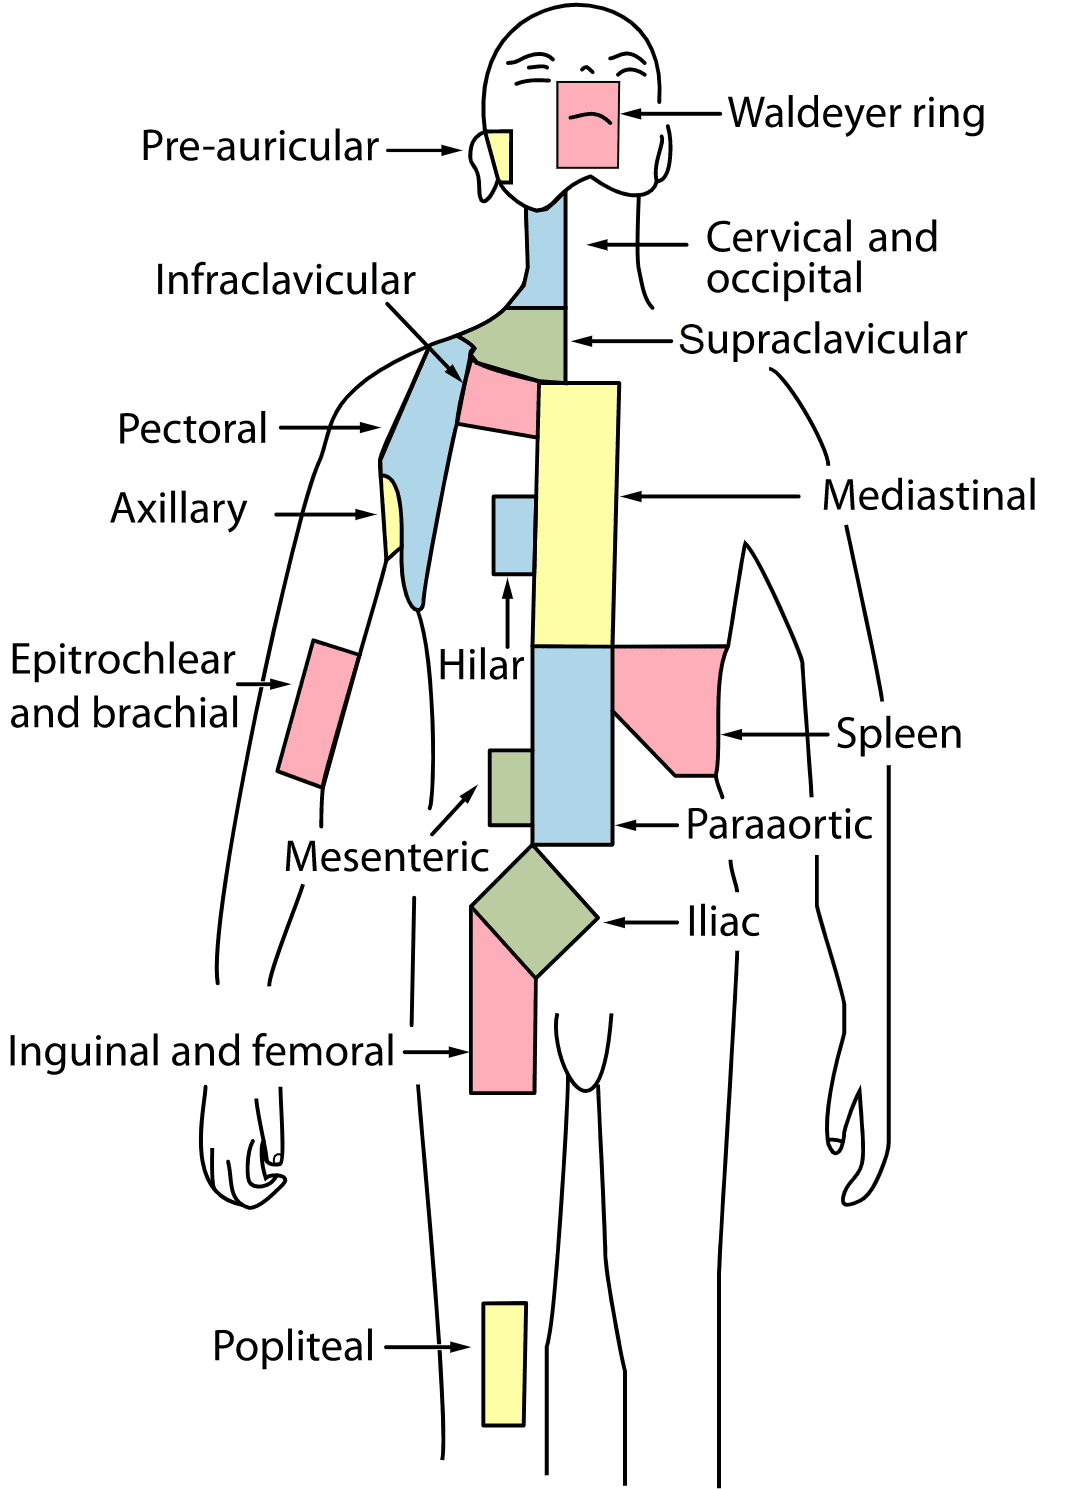

Zones Of Lymph Nodes

Hilar Lymph Nodes Map

Lymph Node Staging Map Used To Standardize Node Locations. | Download

www.researchgate.net

lymph staging standardize

Regional Lymph Nodes | SEER Training

lymph nodes regional lymphoma seer node regions anatomy diaphragm preauricular man above staging cancer hodgkin anatomical

Ann Arbor Staging System | Radiology Reference Article | Radiopaedia.org

radiopaedia lymph nodes anatomy arbor staging radiology cotswolds modified lymphatic spine armpit groin axillary

Ann arbor staging system. Lymph system lymphatic nodes abdomen presentation ppt node mesenteric superior intestinal powerpoint inferior trunk. Hilar lymph nodes map